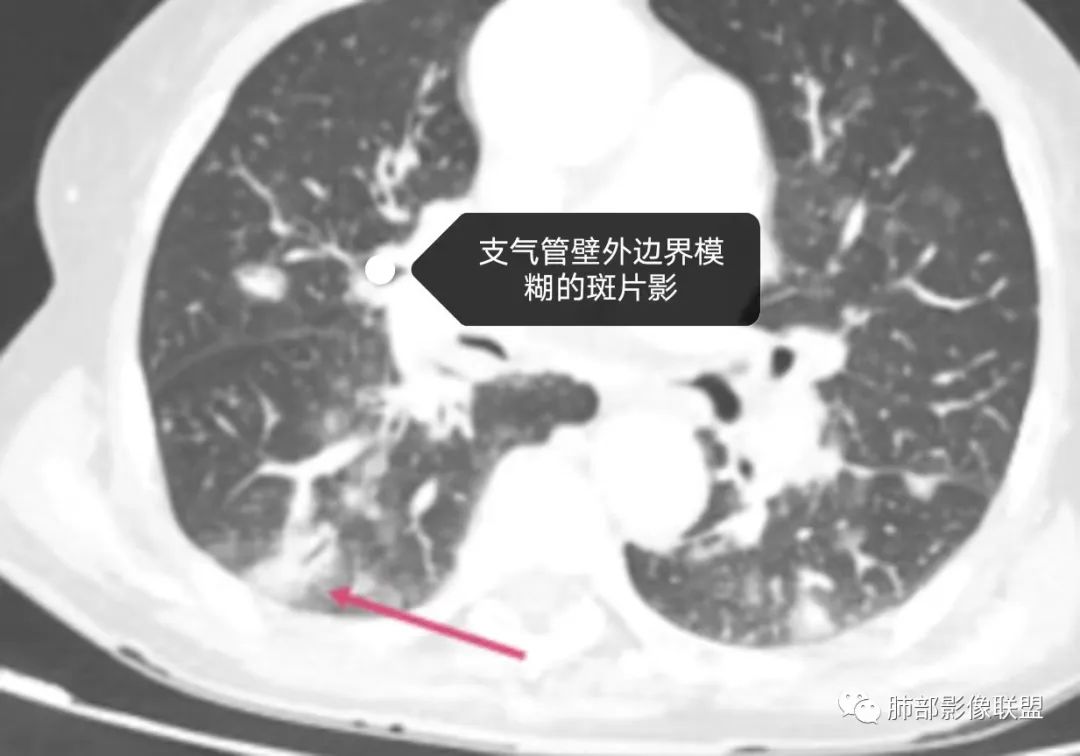

老年女性,三月来两次发热,第一次白细胞计数升高、贫血。第二次白细胞计数不高,LDH升高、低蛋白血症。肺内进行性增多的结节及斑片影,结节见点晕征,斑片影位于支气管血管束,部分支气管壁外见边界模糊的斑片影。有左肾病变。考虑血管炎可能性大。(诊断关键点可能是:点晕征 支气管血管束的斑片影 肾脏病变 第二次发热但白细胞计数不高)

两肺多发病灶,沿支气管血管束分布,缺乏多形性特点,始终未见空洞,没有此起彼伏,没有其他旁证,血管炎的诊断似乎缺乏支撑。

恶性肿瘤自然会纳入视野,如“肺炎型肺癌”(如粘液腺癌、腺癌),转移癌,淋巴瘤(包括淋巴瘤样肉芽肿)等等,有些病灶可以进展比较快。“肺炎型肺癌”、淋巴瘤等病灶常见支气管穿行,来自泌尿系统的透明细胞癌的转移也常常可以气道相关。

淋巴瘤从原发到继发肺浸润,不光可以是表现为典型的大片实变、肿块、结节,还可表现为肺间质的弥漫性浸润、或者散在的斑片影、粟粒样的改变,到单纯围绕中轴间质的增生性改变等等,可以说是变化莫测、扑朔迷离,这给我们的诊断带来很多的困惑和迷茫,但是从点到面再从全身回到肺部,间接的临床影像信息也会给我们带来决定性意义的证据!

原发性肺淋巴瘤是一种影响肺部的单克隆淋巴样增生,患者在最初诊断后至少 3个月内没有可检测到的胸外淋巴瘤。原发性肺淋巴瘤很少见,占所有原发性肺肿瘤的 0.5%。原发性肺部受累的淋巴组织增生性疾病包括黏膜相关淋巴组织起源的结外边缘区淋巴瘤(MALT)、弥漫性大 B 细胞淋巴瘤(DLBCL)和淋巴瘤样肉芽肿(LYG)。MALT淋巴瘤是一种低级别B淋巴细胞淋巴瘤,由具有局灶性浆细胞样特征的单调小淋巴细胞组成。它们由沿远端支气管和细支气管分布的上皮下淋巴滤泡组成。肿瘤可能有许多关联,其中包括:干燥综合征、异常丙种球蛋白血症、淀粉样蛋白沉积、胶原血管病、幽门螺杆菌感染和艾滋病等。其影像学表现复杂多变,通常表现为孤立的、界限清楚的软组织肿块。不太常见的成像特征包括:多个单侧或双侧结节沿支气管血管束和小叶间隔弥漫性浸润、广泛的肺叶浸润、模拟实变(肺炎)、伴有空气支气管征或磨玻璃样改变。这些由外淋巴结节、间隔和支气管血管周围增厚组成的间质模式看起来与癌性淋巴管炎或结节病所见的相同。

中央淋巴道分布(支气管血管束分布)外周淋巴道分布(小叶间隔和胸膜下分布)

①低度恶性的病变可以浸润肺间质但不破坏支气管结构。